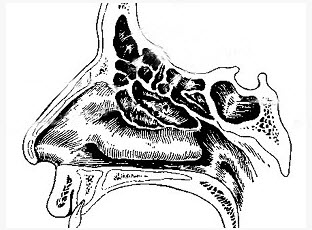

如图,区分前、后筛窦的解剖标志是()。

A . 中鼻甲基板

B . 中鼻甲附着处

C . 下鼻甲附着处

D . 筛前动脉

E . 筛后动脉

如图,区分前、后筛窦的解剖标志是()

[单选题]如图,区分前、后筛窦的解剖标志是()A .中鼻甲基板B .中鼻甲附着处C .下鼻甲附着处D .筛前动脉E .筛后动脉

如图,区分前、后筛窦的解剖标志是()

[单选题]如图,区分前、后筛窦的解剖标志是()A . 中鼻甲基板B . 中鼻甲附着处C . 下鼻甲附着处D . 筛前动脉E . 筛后动脉

如图,分隔前组筛窦与后组筛窦的解剖标志是()。

[单选题]如图,分隔前组筛窦与后组筛窦的解剖标志是()。A . 中鼻甲基板B . 中鼻甲附着处C . 筛前动脉D . 筛后动脉E . 上颌动脉

如图,分隔前组筛窦与后组筛窦的解剖标志是()

[单选题]如图,分隔前组筛窦与后组筛窦的解剖标志是()A .中鼻甲基板B .中鼻甲附着处C .筛前动脉D .筛后动脉E .上颌动脉

如图,分隔前组筛窦与后组筛窦的解剖标志是()

[单选题]如图,分隔前组筛窦与后组筛窦的解剖标志是()A . 中鼻甲基板B . 中鼻甲附着处C . 筛前动脉D . 筛后动脉E . 上颌动脉